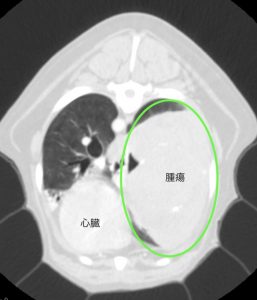

より詳しい診断のためCT検査を行いました。

腫瘍は心臓よりも大きく、右肺後葉に発生していました。

他の肺に転移は認められずリンパ節への転移もありませんでした。